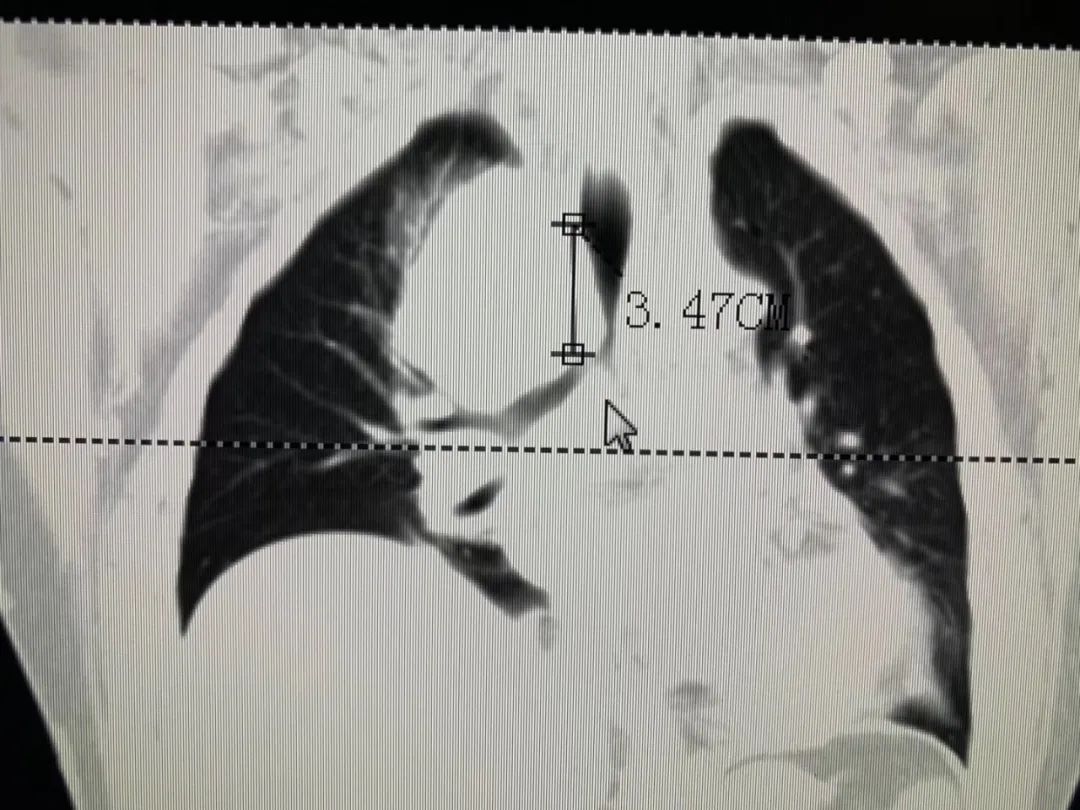

患者金先生因吃飯吞咽困難去當?shù)蒯t(yī)院做電子胃鏡檢查,確診為食管癌,情況很不樂觀。為求進一步診療,金先生先在我院接受了兩次食管癌介入化療,控制腫瘤發(fā)展,改善吞咽困難情況。

牛立志院長表示,患者無手術指征,而介入治療副作用小,患者易于耐受,在改善晚期食管癌患者生活質量的同時,延長患者生存期。此外,術前新輔助化療可以達到明顯降期目的,為根治術手術創(chuàng)造條件。隨著金先生身體逐漸變好,牛立志院長、曾宗淵名譽院長為其開展右側開胸食管癌根治術+三野淋巴結清掃術,經(jīng)過9個小時手術順利完成。